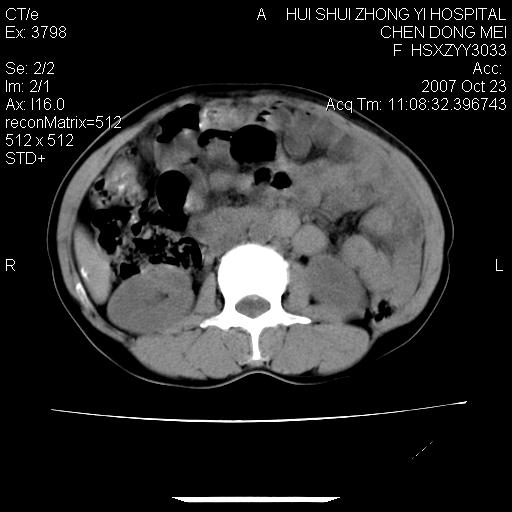

腹腔巨大软组织密度影,边缘光滑,包膜完整,内囊变坏死。腹膜后及盆腔内淋巴结肿大。结合病史考虑卵巢癌可能性大。

病灶内可见脂肪密度影,考虑畸胎瘤可能性大

病变巨大,呈囊实性改变,包膜较厚且完整,内见分膈,周围脏器明显受压移位,病变与左侧附件关系密切,考虑来源左侧附件的囊腺瘤,不除外癌变可能;畸胎瘤可能性较小。

病变巨大,呈囊实性改变,包膜较厚且完整,内见分膈,周围脏器明显受压移位,病变与左侧附件关系密切,考虑来源左侧附件的囊腺瘤,盆腔内见肿大淋巴结,不除外癌变可能。

病变巨大,呈囊实性改变,包膜较厚且完整,内见分膈,周围脏器明显受压移位,病变与左侧附件关系密切,考虑来源左侧附件的囊腺瘤,不除外癌变可能